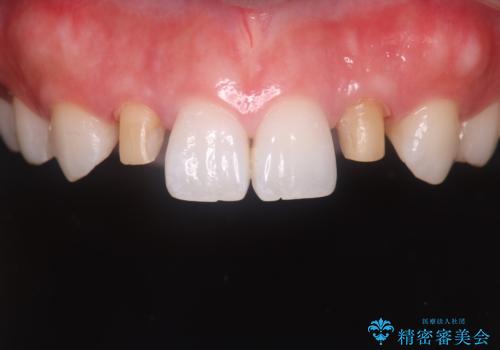

- 食べ物が歯間にはさまることを主訴に来院された患者様です。レントゲンより上顎両側切歯に根管治療が実施されていますが、被せ物が入っておらず、充填物に劣化像もみられました。歯の色の差も気にされていたのでオールセラミッククラウンにて治療いたしました。